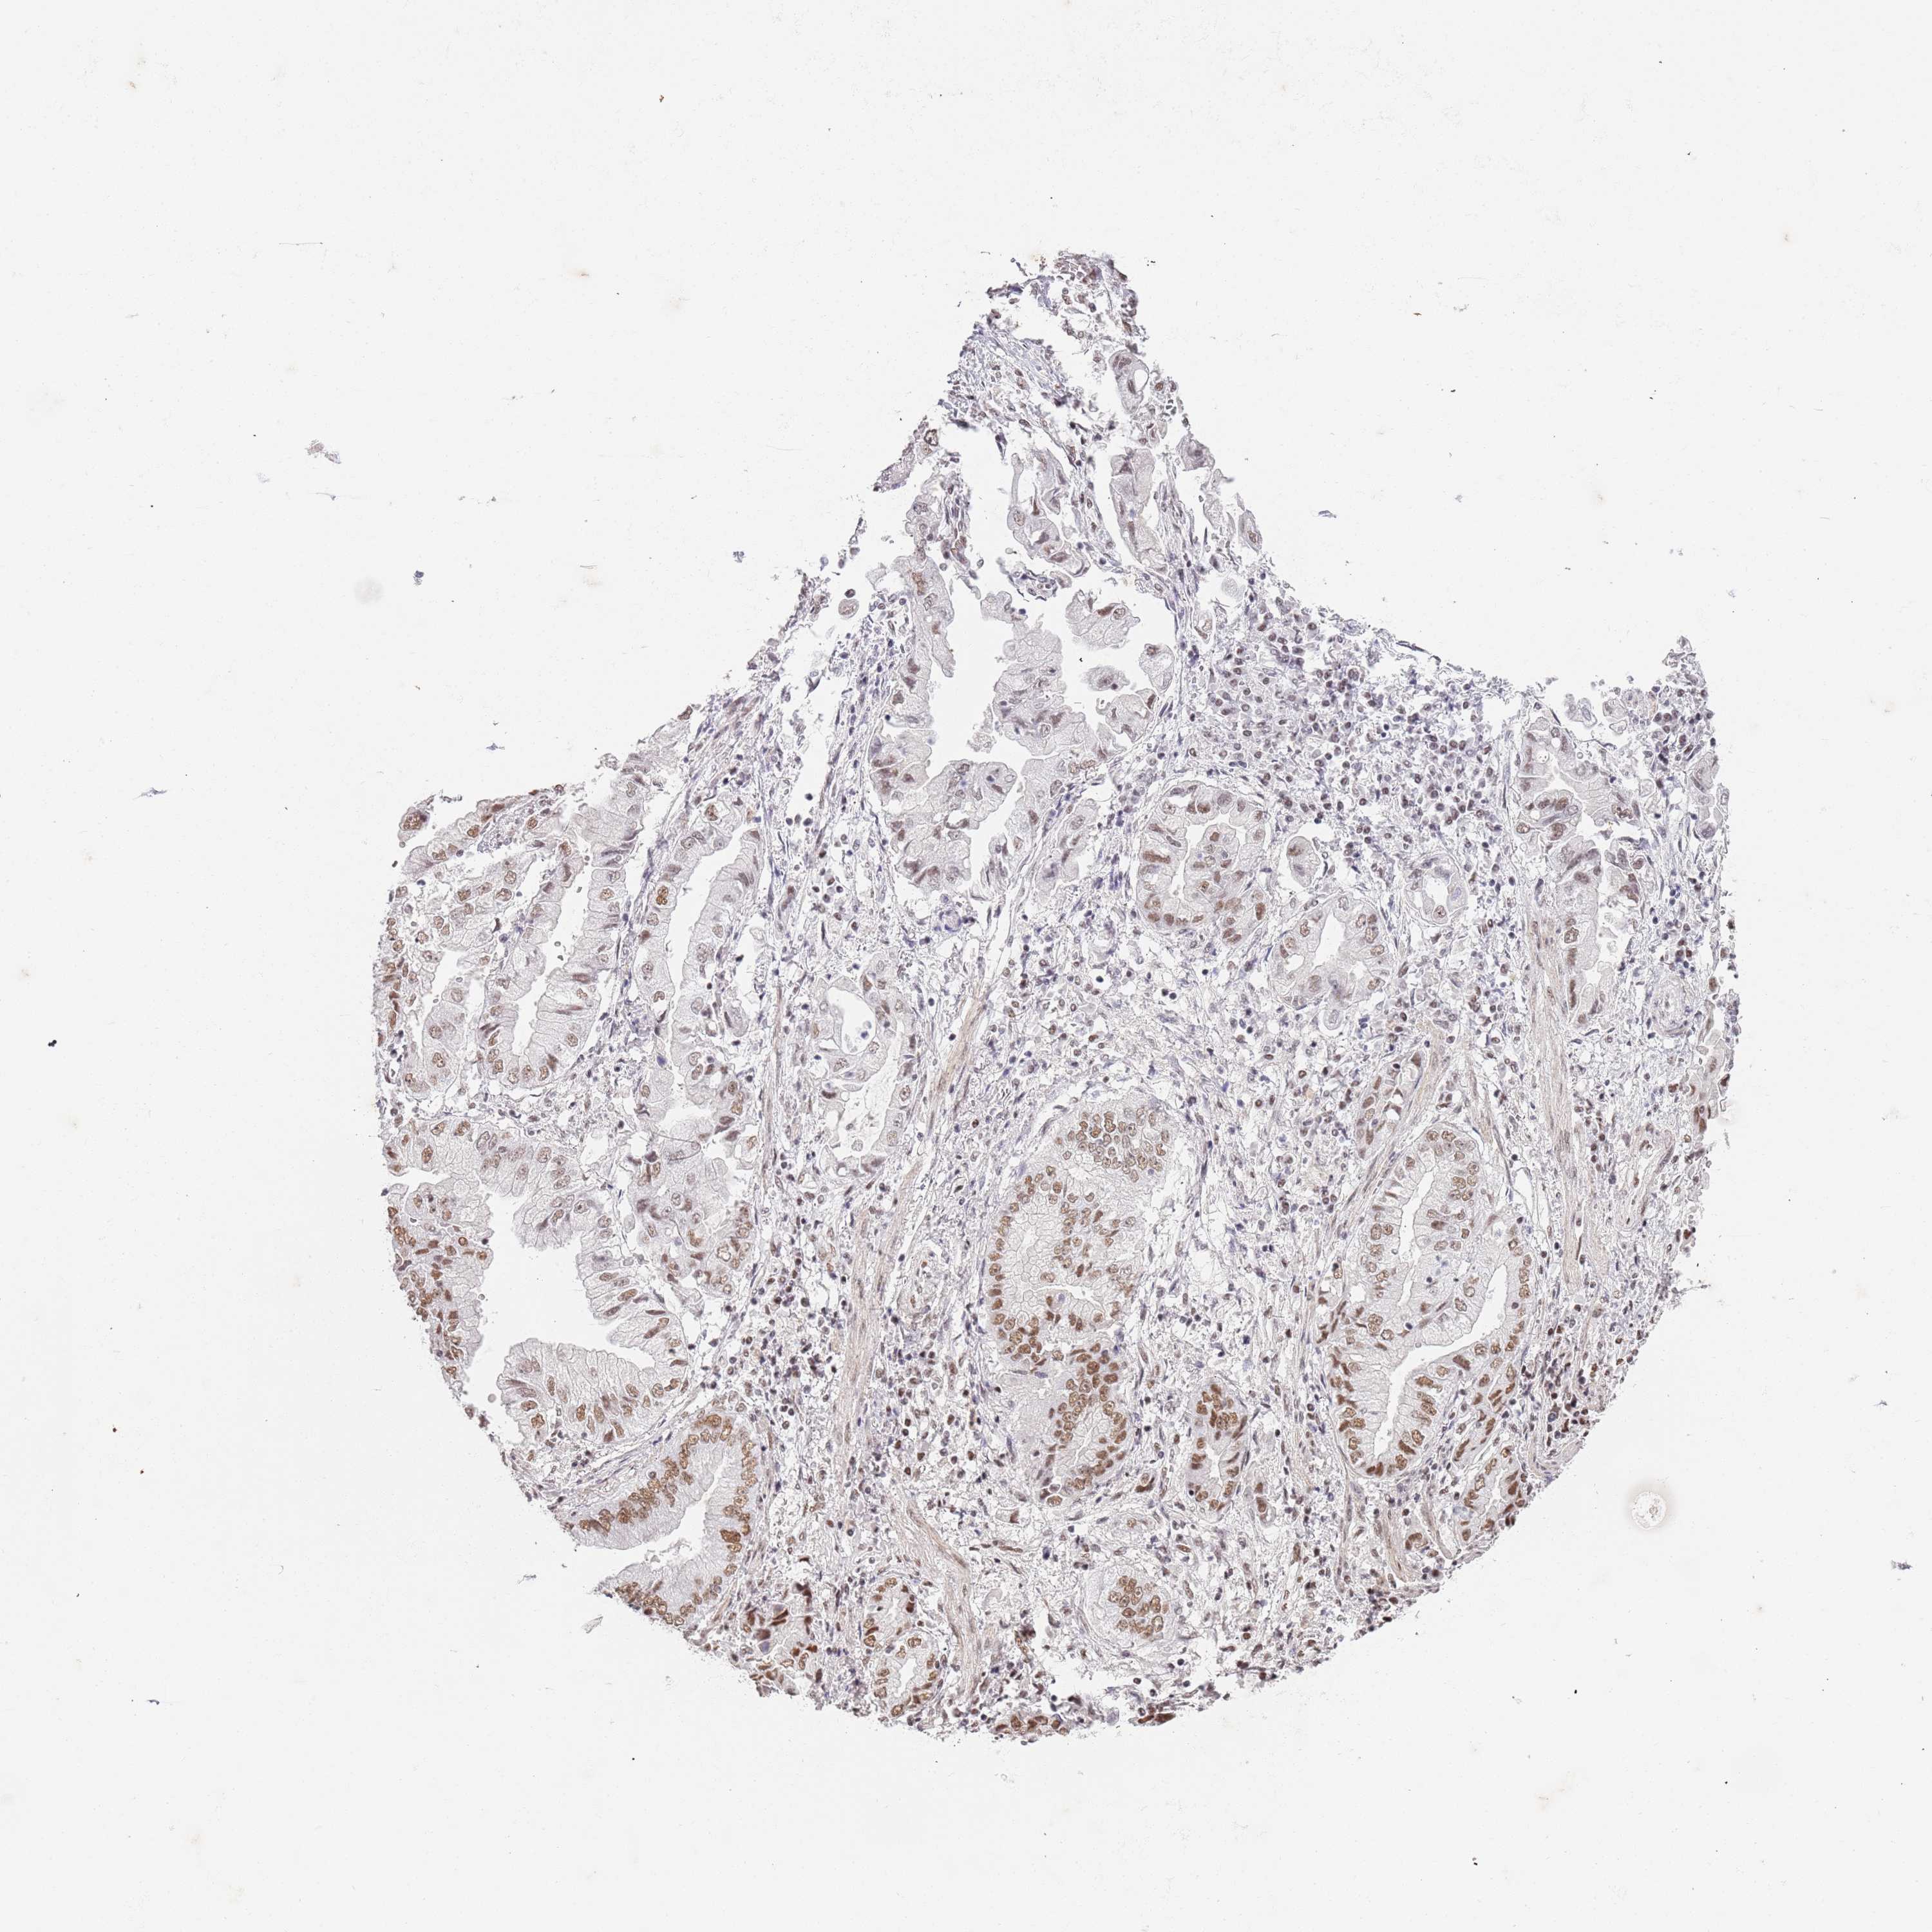

STOMACH CANCER - Protein expressioni

A mouse-over function shows sample information and annotation data. Click on an image to view it in a full screen mode. Samples can be filtered based on level of antibody staining by selecting one or several of the following categories: high, medium, low and not detected. The assay and annotation is described here.

Note that samples used for immunohistochemistry by the Human Protein Atlas do not correspond to samples in the TCGA dataset.

Antibody stainingi

Antibody staining in the annotated cell types in the current human tissue is reported as not detected, low, medium, or high, based on conventional immunohistochemistry profiling in selected tissues. This score is based on the combination of the staining intensity and fraction of stained cells.

Each image is clickable and will lead to virtual microscopy that enables deeper exploration of all samples and also displays staining intensity scores, fraction scores and subcellular localization as well as patient and tissue information for each sample.

Antibody HPA042485

Antibody HPA042546

Staining

High

Medium

Low

Not detected

Intensity

Strong

Moderate

Weak

Negative

Quantity

>75%

75%-25%

<25%

None

Location

Nuclear

Cytoplasmic/membranous

Cytoplasmic/membranous,nuclear

Adenocarcinoma, NOS